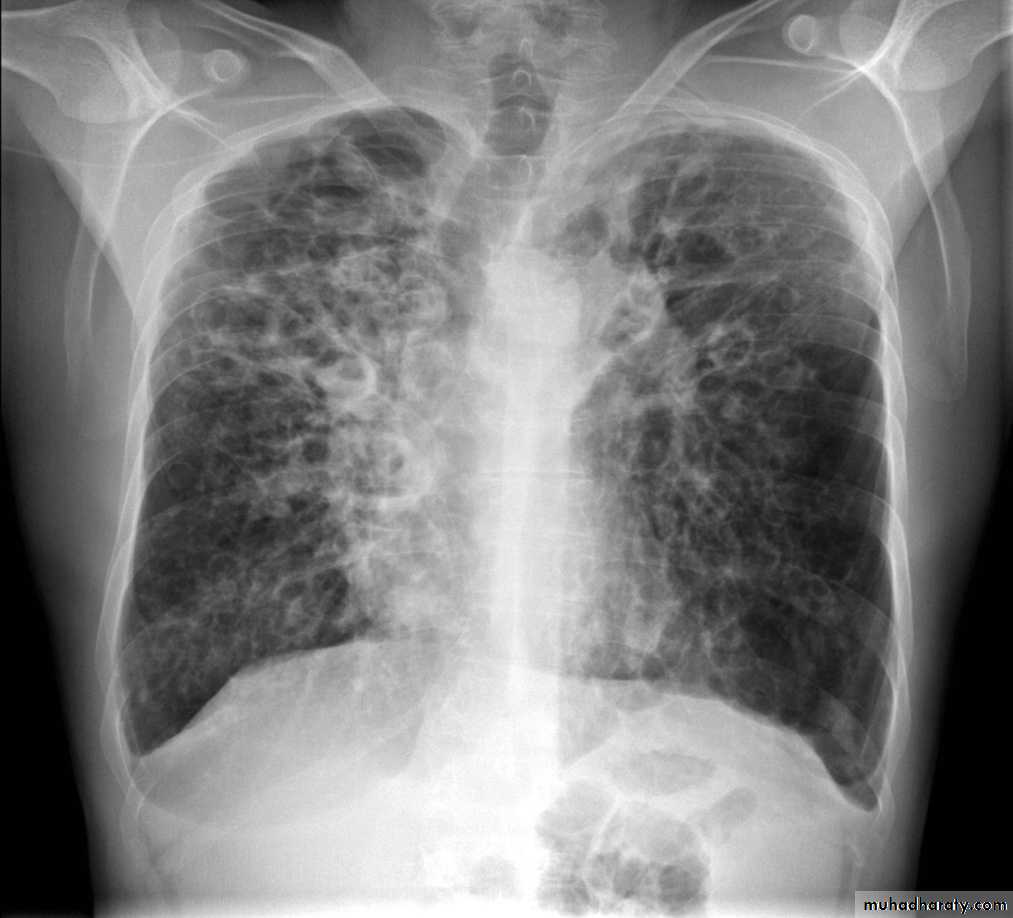

• 1-CXR :The plain chest radiograph is abnormal but generally nondiagnostic, the common findings are

• increased lung markings,

• atelectasis,

• air-fluid levels

• Cavities which fill and empty on serial CXR

• Honey-comb pattern: areas of destroyed lung with compensated overinflated adjacent parenchyma